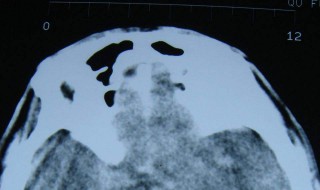

1、侧脑室、第三脑室增宽。脑积水的可能性大。而脑积水的现象除了脑室增宽外,还有一个明显的伴随症状是脊柱裂。

2、脑积水的治疗,主要是手术治疗,可做侧脑室腹腔引流术。多数三甲医院都能做这样的手术。

3、现在很多胎儿侧脑室增宽10-15mm生下来照样非常健康的!